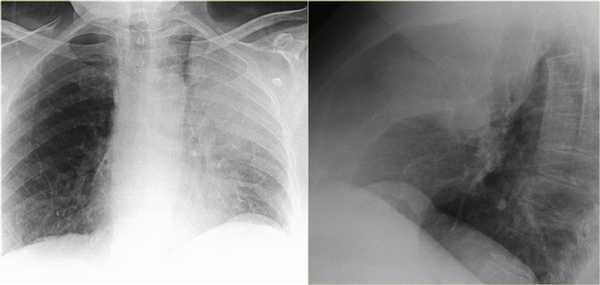

Ателектаз нижней доли левого легкого

На рентгенограмме визуализируются изменения трехгранной формы высокой плотности, расположенные позади тени сердца, что хорошо выявляется на боковом снимке. На боковом снимке при оценке контура диафрагмы спереди назад определяется все менее четко. Исходя из названия раздела напрашивается диагноз — ателектаз нижней доли левого легкого. В норме прозрачность легкого внизу выше, а в нашем случае наоборот (синяя стрелка).

На рентгенограмме органов грудной клетки определяется тотальный ателектаз правого легкого со смещением средостения вправо. На втором снимке представлен тот же пациент, но после лечения. Легкое воздушное и положение средостения в норме. Распространенной причиной тотального ателектаза является неправильно установленная вентиляционная трубка, которая расположена слишком низко и тем самым обтурирует главный бронх.

На ниже представленном снимке представлен пациент с тяжелой бронхопневмонией и тотальным ателектазом. Причиной ателектаза явилось обтурация бронха слизью. После отсасывания мокроты аэрация левого легкого была восстановлена.

На ниже представленной рентгенограмме пациента с карциноматозом плевры левое легкое полностью компрессируется плевральной жидкостью (левый гемоторакс). В выше представленных случаях был обтурационный ателектаз, а в этом компрессионный, что лучше визуализируется на КТ (синяя стрелка). КТ данному пациенту также проводили по причине легочного эмболизма (красная стрелка).